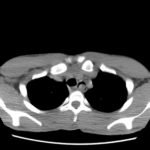

Significant findings:

After an unremarkable chest radiograph was obtained, a computed tomography (CT) scan of the chest was obtained due to possible co-ingestion of bones to rule out perforation. The CT scan demonstrated focal distention of the mid-esophagus due to an impacted food bolus (white arrow). An aberrant right subclavian artery (yellow arrow) was located just distal to the impaction site with partial compression of the esophagus (red arrow).